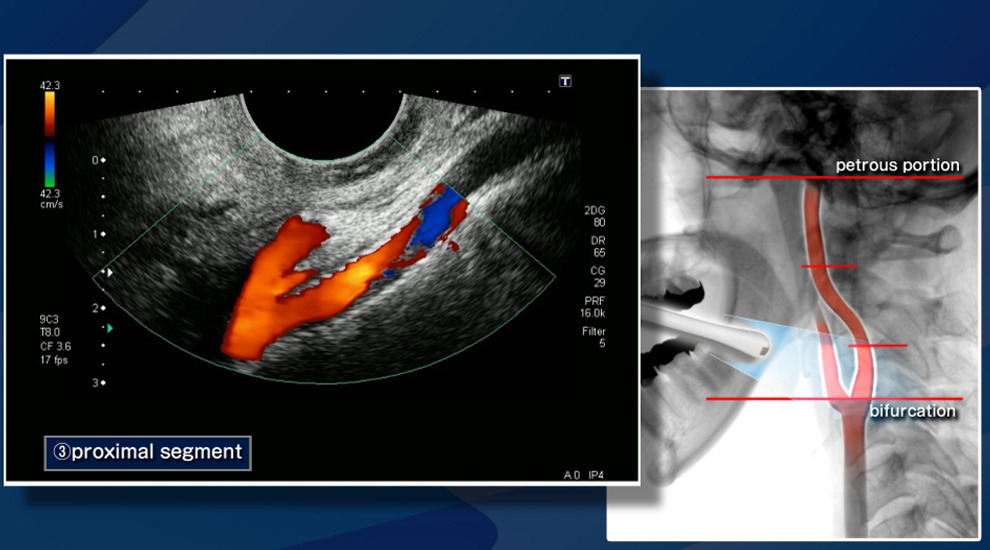

- 젤을 바른 후 초음파 탐촉자를 경동맥 위에 대고 영상 관찰

- 혈류 속도 측정과 플라크 유무 확인

- 혈류 속도 증가 여부